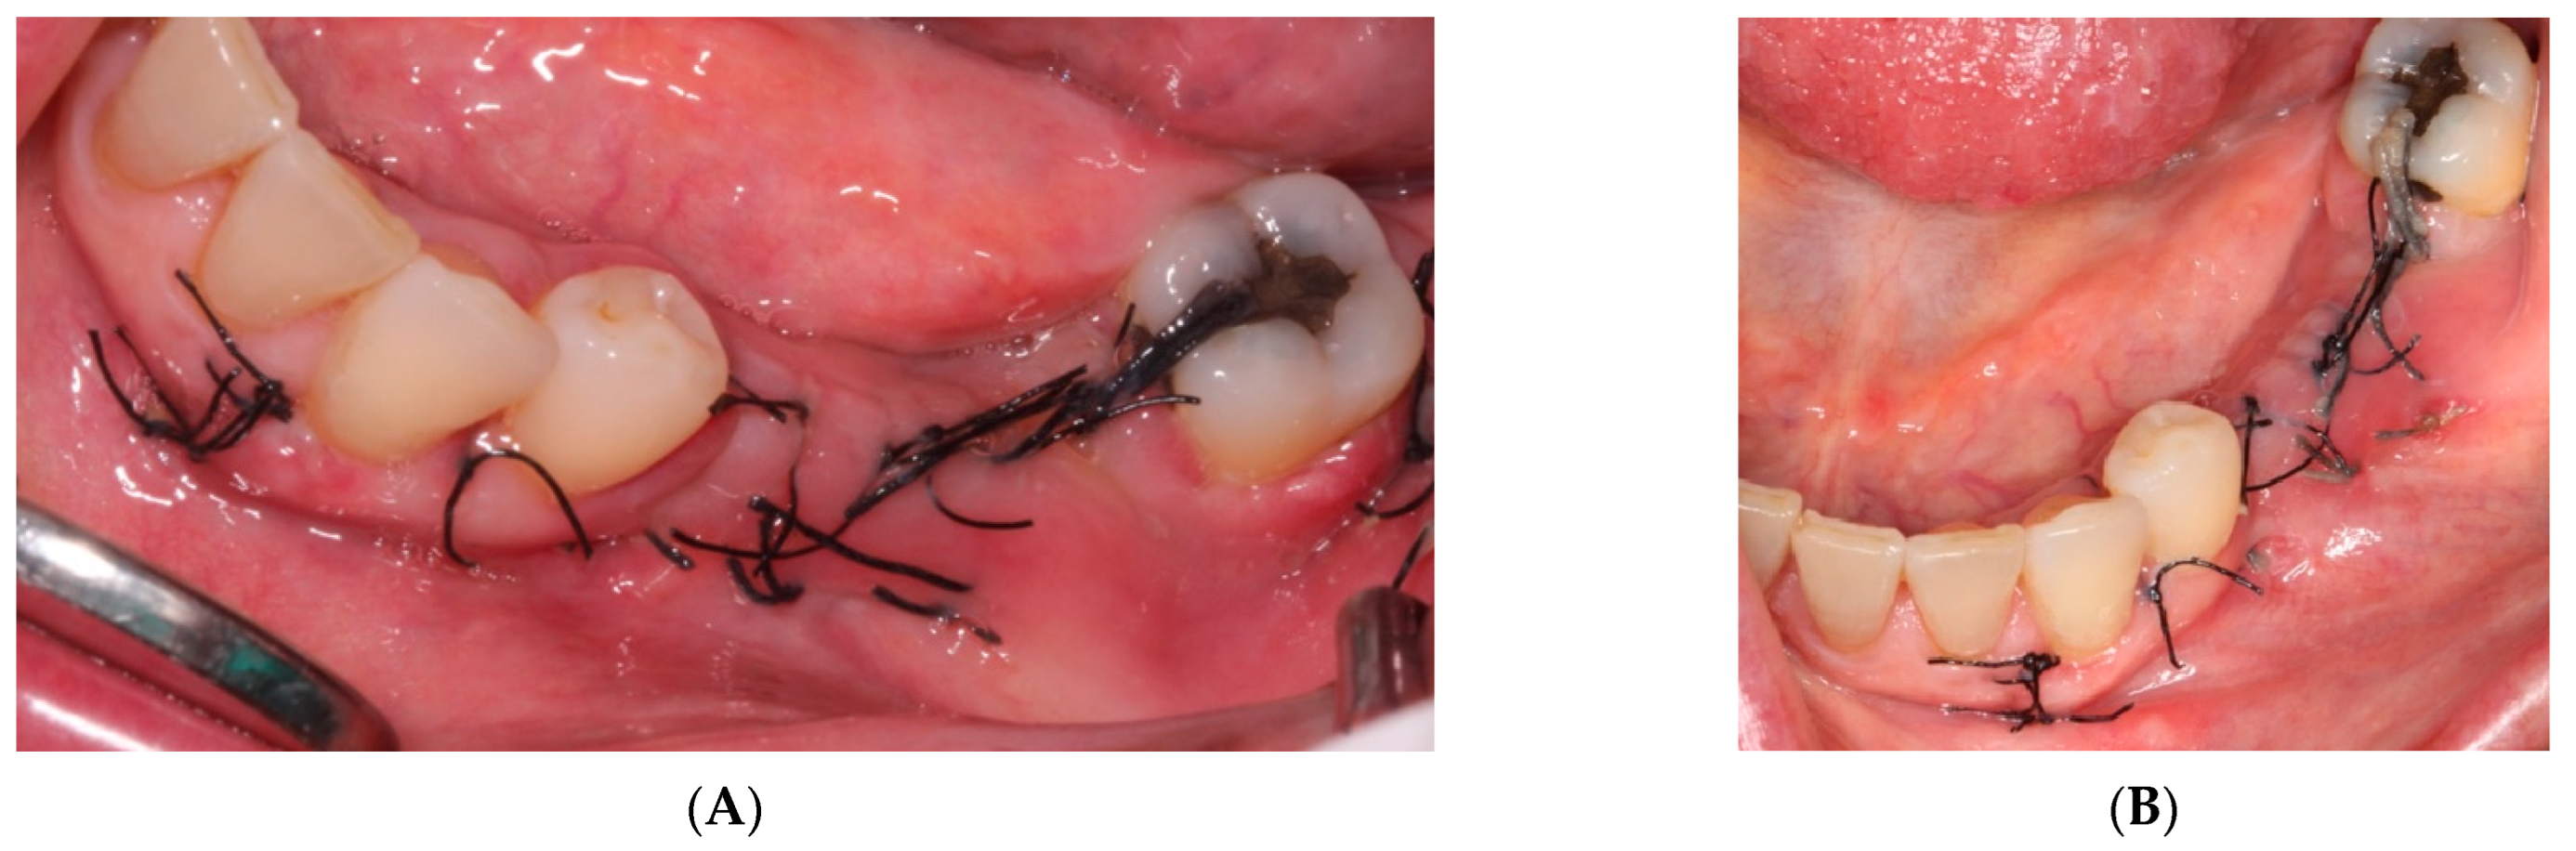

- The sutures were removed on day 21. A panoramic radiograph was taken after surgery. (Figure 8). Periodic controls were scheduled; every week during the first 2 months, every two weeks in the third and fourth months, and once a month up to 6 months.

- On the day of surgery, the titanium mesh and the microscrews were removed (Figure 9). When the mesh was removed, a soft consistency was observed in the most coronally newly formed bone and it was decided to postpone the placement of the implants and allow it to ossify for another month and a half. A panoramic radiograph was taken after surgery (Figure 10).